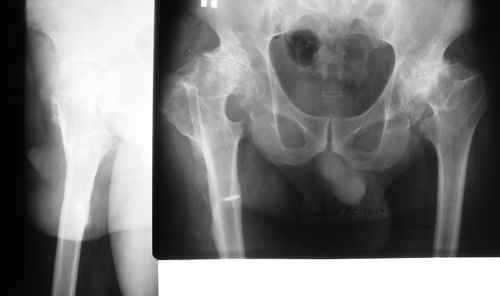

Эндопротезирование на фоне деформации после остеотомии бедра

пациент 60 лет.В 1980 году медиализирующая остеотомия правого бедра с фиксацией пластиной Петуховой.

В 2006 году произведено удаление пластины.В настоящий момент планируется эндопротезирование правого тазобедренного сустава.

В наличии эндопротезы De-Puy Corail, AML; Biomet, ножка Taperloc.

Возможные варианты установки ножки:

1)установить ножку в оси диафиза

2)установить ножку в вальгусном положении

3)выполнить поперечную остеотомию бедра на уровне смещения с последующим остеосинтезом ножкой эндопротеза.

Наш опыт подсказывает нам, что предпочтительнее всего использовать ножки Вагнера. В круглом канале она фиксируется лучше всего, кроме того, у Вас не будет проблем с антеверсией.

Из имеющихся вариантов предпочел бы анатомическую AML по каналу (обломок винта высверлить с медиальной стороны кости), это позволит сохранить офсет головки относительно трохантера. Аутопластика калькара с фланцевым остеосинтезом 1-2 спицами.

Заказали ножку Вагнера. По скиаграммам посмотрели должно получиться нормально.